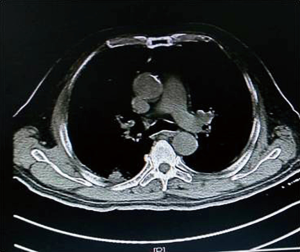

As illustrated in Table 3, tumors were significantly reduced in all 6 patients after the implantation of radioactive particles. A typical case can be seen in Figures 4,5.

As shown in Figure 7 and Figure 3, there were 2 CRs and 4 PRs after follow-up for 1 month, indicating a response rate (RR) of 6/6, and a disease control rate (DCR) of 6/6; six patients were followed up for 6 months, including one patient who refused follow-up visit (still alive),while the other 5 patients were followed up regularly, including 3 CRs and 2 PRs; five patients were followed up for 12 months, including 3 CRs, 1 PR and 1 PD, indicating an RR of 4/5, a DCR of 4/5, and a progression rate of 1/5; four patients were followed up for 18 months, including 3 CRs and 1 SD, indicating a RR of 3/4 and a DCR of 4/4; four patients were followed up for 24 months, including 1 patient who refused a follow-up visit (still alive), while the other 3 patients were still followed up regularly; there were still 4 patients who were followed up for 30 months, including 1 patient who refused follow-up visit (alive) and 3 patients who were followed up on a regular basis; one patient was followed up for 36 months and had a recurrence of primary lesion, with the response being evaluated as PD. In addition, Figure 7 shows that patient E achieved significant response after implantation of 125I particles, and the response was evaluated as CR 1 month after implantation (Figures 8,9); however, the primary lesion recurred and was enlarged with left lung metastasis in month 12 (Figures 10,11), whereupon the response was evaluated as PD. The patient was given CT-guided implantation of 125I radioactive particles again for treatment of the recurrent lesion. The repeated pulmonary CT after re-implantation showed significant reduction of tumor (reduction rate 27.32%), as shown in Figure 12, and the response was subsequently re-evaluated as SD.

Other relevant studies have shown a unique advantage of implantation of radioactive particles in the treatment of lung cancer. In a study by Lu et al. (10), 15 patients with obstructive pneumonia caused by central type lung cancer were given a bronchoscopic implantation of 125I radioactive particles, and followed up in months 2, 6, 12, 18 and 24 after implantation. The median survival was 15.6 months, and the one-year lung recruitment rate was 80.0%, which significantly improved the quality of life. To compare, in our study’s response evaluation from regular follow-up of patients who received the CT-guided implantation of radioactive 125I, it was found that the tumors had significantly shrunk in all 6 patients. Typical cases are illustrated in Figures 4 and 5, and as can be seen in Figure 6, the most obvious reduction of tumor was seen in the 6th month of follow-up. In the 5 patients who were followed up, there were 3 CRs, indicating an RR of 5/5 (100%) and a DCR of 5/5 (100%). This shows that the implantation of radioactive particle achieved the best response within 6 months in the treatment of early lung cancer. In addition, as Figure 3 shows, 5 patients were followed up 1 year after implantation and had a survival rate of 5/5 (100%), 4 patients were followed up 2 years after implantation and had a survival rate of 4/4 (100%), and the longest time after enrollment was up to 3 years and 5 months; at the time of writing, this patient is still alive. The observations above demonstrate the significant efficacy of the implantation of 125I radioactive particles in treatment of early lung cancer.